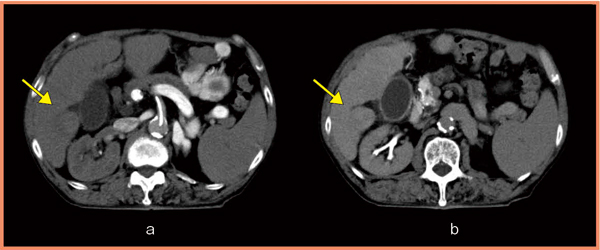

HCCでは,さまざまな転移,再発を経験するが,治療後の予後予測には,結節からのdrainage veinを把握することが重要である。大きな結節のdrainage veinについて,DSAでは確認できなかった症例が,IVR-ADCTの3D,4D-CT撮影により,肝静脈であることが確認できた(図2)。ADCTは濃度分解能が高く,かつ,ボリュームの4D撮影によって,血行動態を任意の方向から確認できるため,DSAでは造影効果の低いdrainage veinの描出も可能となる。本症例のように,肝静脈へのドレナージが把握できれば,今後,転移・再発形式の予測,それによる治療法の変更などが可能となる。例えば,門脈にドレナージされる場合には,肝内転移を考慮する必要があり,一方,肝静脈にドレナージされる場合は,肝外転移の可能性を考慮する必要があるなど,治療の予後予測にも有用と考えられる。

図2 4D-CTによるHCCのdrainage veinの描出

肝静脈(↓)がdrainage veinであることがわかる。